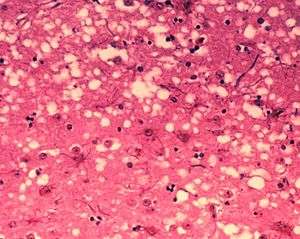

| Microscopic "holes" are characteristic in prion-affected tissue sections, causing the tissue to develop a "spongy" architecture. | |

Prions cause neurodegenerative disease by aggregating extracellularly within the central nervous system to form plaques known as amyloid, which disrupt the normal tissue structure. This disruption is characterized by "holes" in the tissue with resultant spongy architecture due to the vacuole formation in the neurons.[50] Other histological changes include astrogliosis and the absence of an inflammatory reaction.[51] While the incubation period for prion diseases is relatively long (5 to 20 years), once symptoms appear the disease progresses rapidly, leading to brain damage and death.[52] Neurodegenerative symptoms can include convulsions, dementia, ataxia (balance and coordination dysfunction), and behavioural or personality changes.